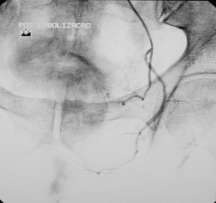

8. 双侧前列腺动脉栓塞

9. 终点(end point):前列腺动脉血流缓慢或接近停滞(near stasis),与栓塞前前列腺动脉造影比较,前列腺动脉血流中断(interruption)前列腺血管床(prostate bed opacification)不显影。